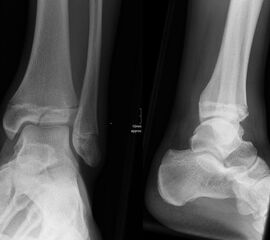

Übergangsfrakturen weisen häufig nur eine geringe Dislokation auf (Abb. 25). Möglicherweise wurden diese Verletzungen in ihrer Rolle hinsichtlich einer Arthroseentwicklung lange Zeit überbewertet 13. Nicht dislozierte Frakturen können konservativ behandelt werden.

Nach einer primären Ruhigstellung im gespaltenen Unterschenkelgipses kann dieser nach Abschwellung geschlossen werden. Nach 10 Tagen erfolgt der Wechsel auf einen geschlossenen Unterschenkel-Kunststoffgips für weitere 3-4 Wochen. Da sehr kleine Kinder aus Unterschenkelgipsen gerne herausschlüpfen, sollte in diesen Fällen an die Möglichkeit der anfänglichen Oberschenkelgipsanlage gedacht werden. Die immer wieder genannte Sarmiento-Gipsanalge hat für uns bei der Behandlung von Sprunggelenksverletzungen im Kindesalter keinen Stellenwert. Den Indikationsbereich des Sarmiento-Gipses mit Freigabe der Mobilität im Kniegelenk in einem Bewegungsausmaß von 0-30-120° und Lastreduzierung für den Unterschenkel durch eine Abstützung an den Femurkondylen, sehen wir vor allem bei der diaphysären Unterschenkelfraktur.

Dislozierte Frakturen (Frakturspalt > 2 mm) werden grundsätzlich operativ behandelt. Die Reposition kann arthroskopisch unterstützt erfolgen. Die Schraubenosteosynthese erfolgt entsprechend dem Frakturverlauf. Bei Twoplain Frakturen ist meist eine epiphysäre Schraube ausreichend die von lateral kommend das Fragment nach medial-proximal fixiert. Der Schraubenverlauf ist üblicherweise von lateral ventral nach proximal dorsal medial (Abb. 24). Nach Reposition darf in der seitlichen Aufnahme des Sprunggelenks, als auch in der 45° Außenrotationsaufnahme keine Stufe in Höhe der Wachstumsfuge erkennbar sein. Eine sichtbare Stufe ist Indikator für eine unzureichende Reposition.